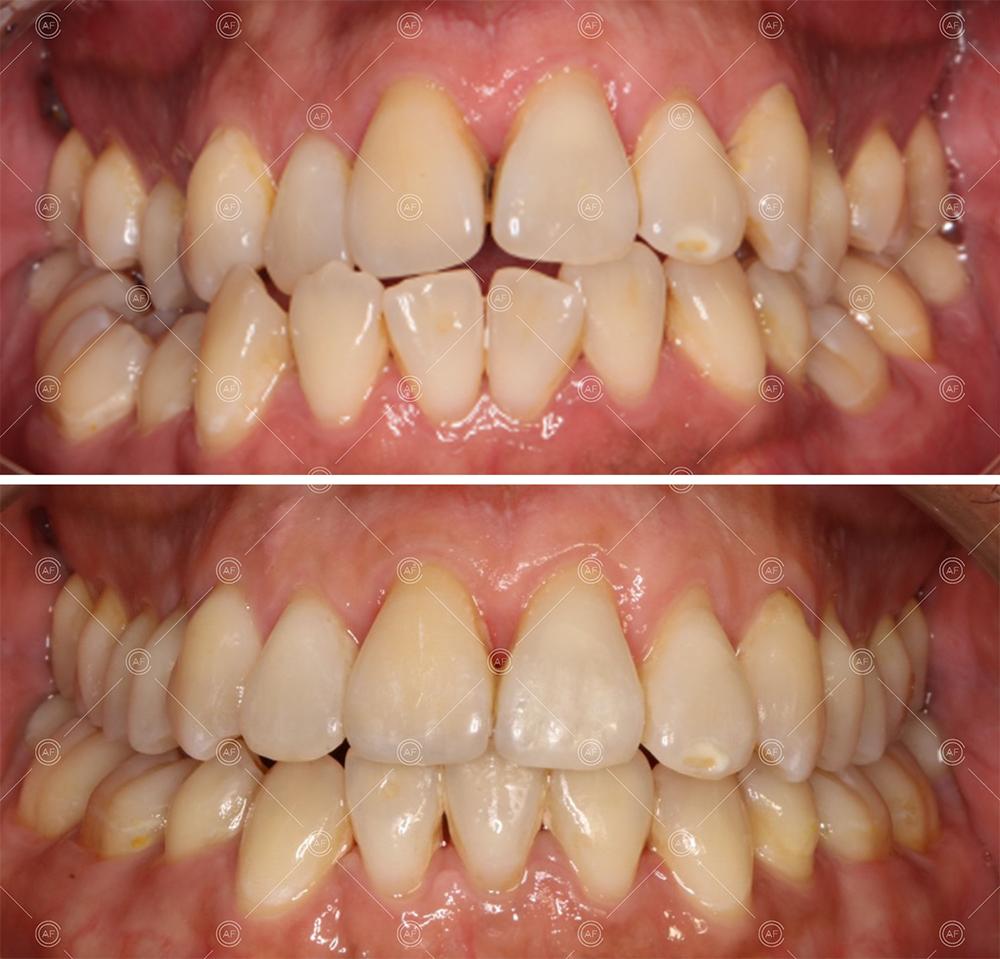

MH debonded in December 2020, with overall treatment time of around 14 months.

She was provided with upper and lower vacuum form retainers, and asked to wear these every night for the first year, and alternate nights for the second year onwards, indefinitely for as long as she wanted her teeth to remain straight. High quality finish was maintained at one year post-debond.